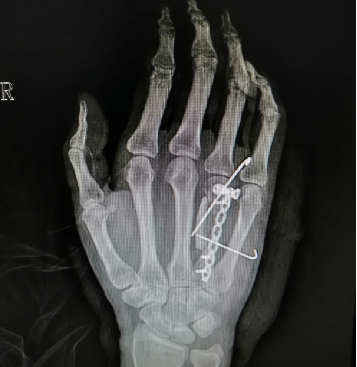

病例2:女性患者,42岁,1年半之前因摔伤到宁波某医院诊疗,行“第4掌骨骨折切复钢板螺钉内固定术”。术后一年半复查发现内固定钢板断裂并骨折未愈合,因此患者转来我院就诊。 入院前影像学检查提示:右手第4掌骨骨折线清晰,边缘硬化,内固定钢板折断。

手术方案:内固定拆除,取髂骨,第4掌骨植骨钢板螺釘内固定术。术中给予骨不连两端截去硬化灶;截取髂骨塑型嵌入。

经管医师汇报了手术过程中,特别是植骨过程中的重要细节,如如何取髂骨应对去除骨折端硬化灶后出现的1cm宽缺隙。对于该患者,还需要继续加强术后沟通交流,很可能会采取PRP治疗以促进骨折愈合。

刘立春副院长建议,术后加支具,有利于骨折部位的愈合。